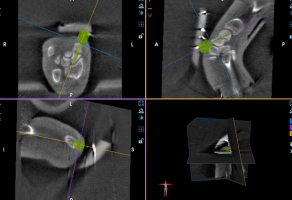

齐伟亚主任、唐洪伟手术团队为王阿姨进行了“机器人导航+关节镜辅助下左舟骨骨折复位内固定术”。术中通过关节镜探查腕中关节间隙,见骨折段相对稳定,通过机器人进行三维影像扫描,医生在导航系统屏幕上设计好钉道规划入路,机器进行精确模拟后,植入接骨钉固定舟骨骨折端,再用C型臂透视检查,各位置均已复位良好,手术顺利结束。

机器人导航精准设计